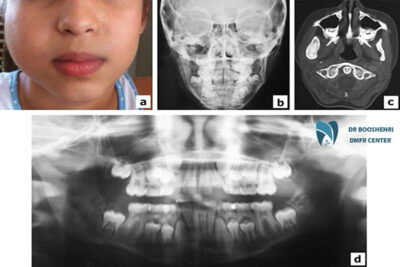

Advancements in technology have introduced various techniques for child jaw imaging. Today, methods such as panoramic radiography, cephalometry, and CBCT (Cone Beam Computed Tomography) provide a more detailed assessment of jaw and dental structures. These techniques offer high-quality images that significantly enhance child jaw diagnosis.

Panoramic radiography is one of the most common child jaw imaging methods, offering a full view of the upper and lower jaw. It is highly useful for detecting child jaw problems like jaw abnormalities, unerupted teeth, and overall structural analysis. Additionally, CBCT provides three-dimensional imaging, allowing a more precise evaluation of the jaw and dental anatomy.